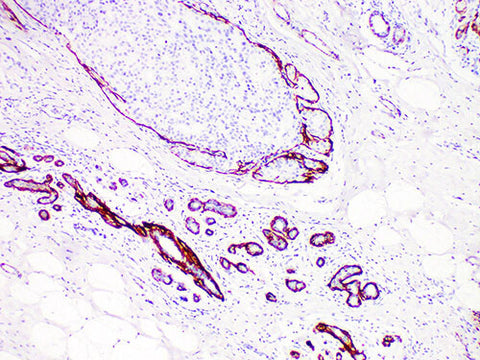

Calponin Monoclonal Antibody Synonyms Calponin

Applications IHC-P

Tissue Specificity Breast cancer

Anti-Calponin can label myoepithelial cells and basement membrane, which can distinguish micro invasive breast cancer and ductal carcinoma in situ. It is also a useful marker of papillary breast disease.